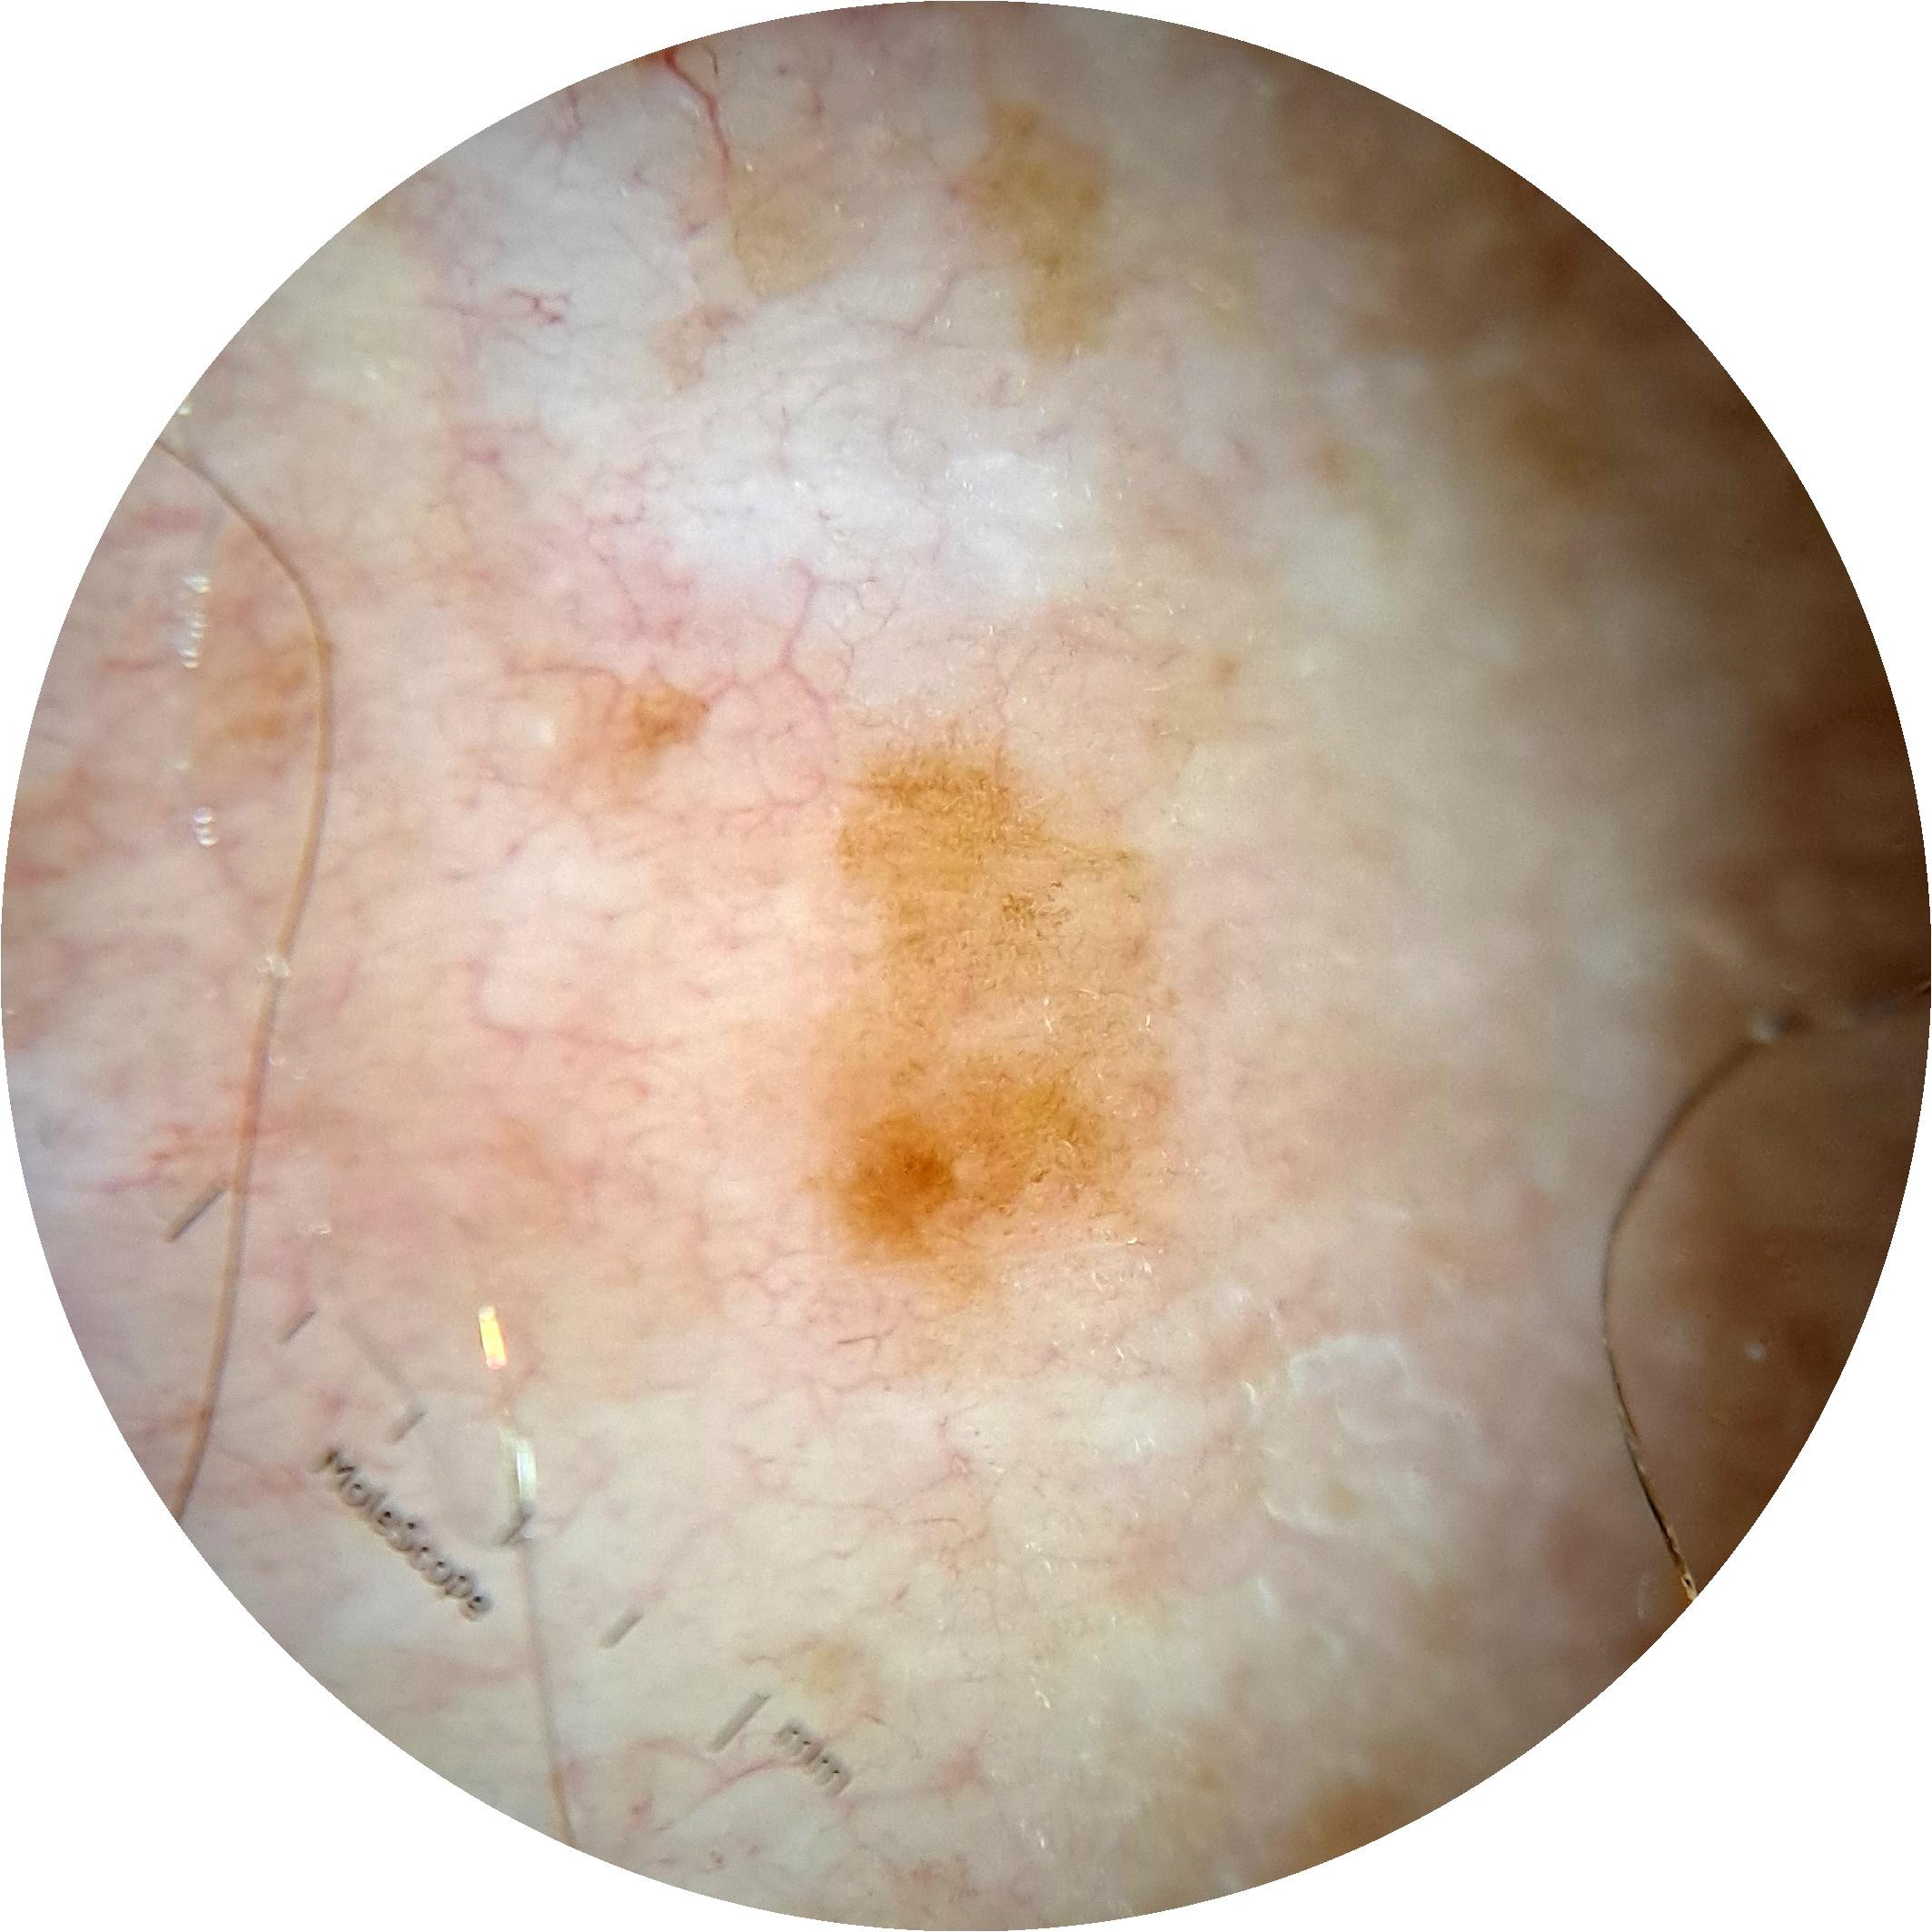

ISIC_6813604

MEL-SELF Trial, https://www.sydney.edu.au/medicine-health/our-research/research-centres/melself-project.html

acquisition_day 624

age_approx 75

anatom_site_1 Head and neck

anatom_site_general head/neck

diagnosis_1 Benign

diagnosis_confirm_type single image expert consensus

fitzpatrick_skin_type I

image_type dermoscopic

personal_hx_mm True

sex male